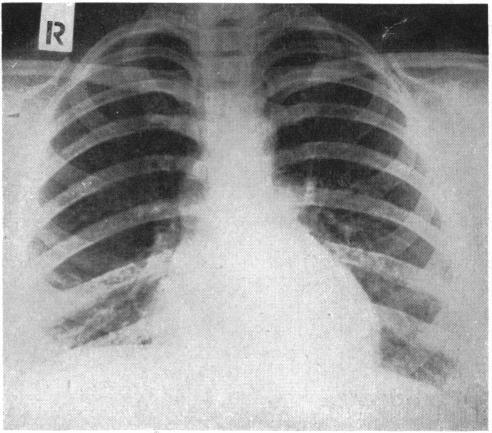

Atypical pneumonia.

Br Med J. 1950 Dec 30;2(4695):1457-61. doi: 10.1136/bmj.2.4695.1457.